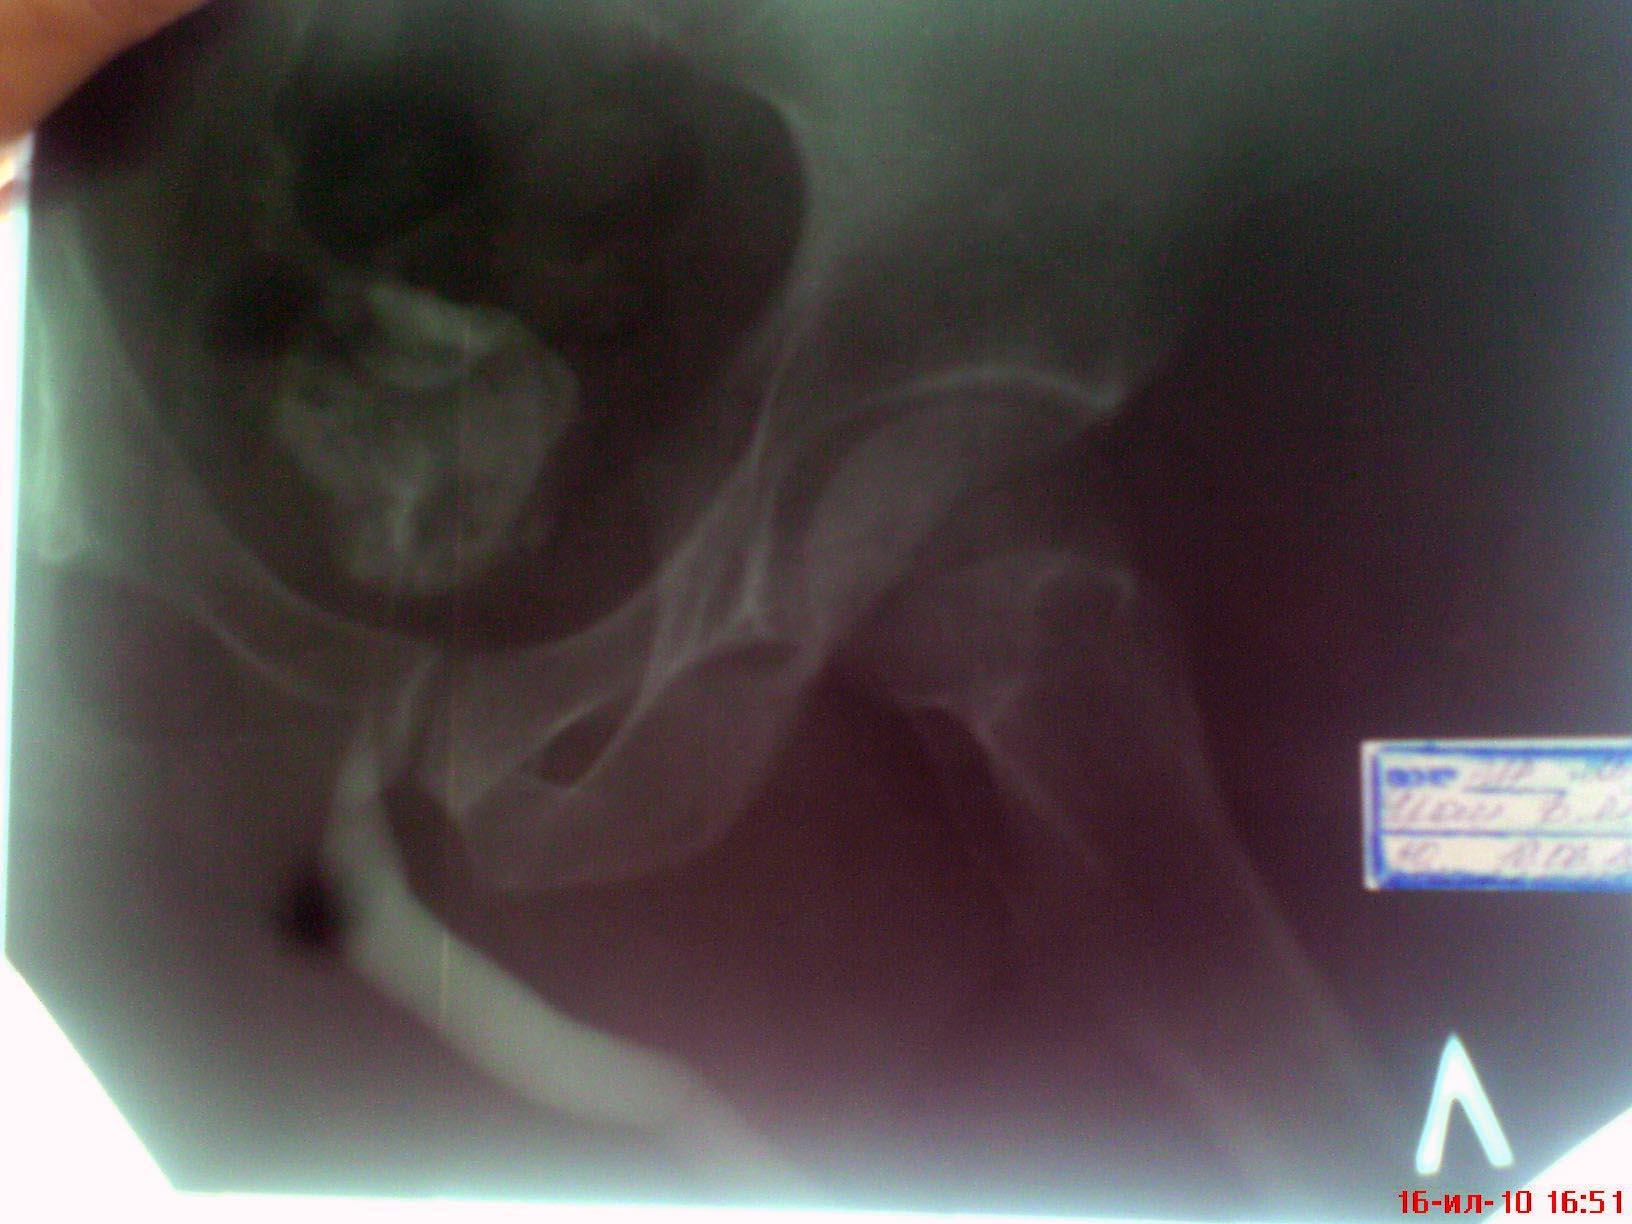

Возможно у Вас проконсультироваться таким образом,я вышлю Вам снимки уретрограмм а Вы скажете свое мнение.